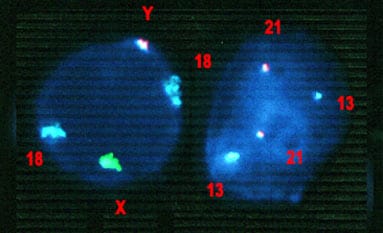

Investigadores de la Universidad de Granada han desarrollado la primera Guía Clínica dirigida a médicos y pacientes sobre el Síndrome de Insensibilidad Androgénica (SIA). Esta enfermedad rara es capaz de provocar un tipo de sexo reverso, situación que se da cuando la persona tiene una apariencia externa de mujer pero una dotación genética masculina. El SIA tiene una baja prevalencia (afecta a una de cada 2.000 personas) y se caracteriza por la resistencia de los tejidos diana a la acción de las hormonas masculinas, lo que impide en individuos cromosómicamente varones (esto es, 46,XY) el desarrollo masculino normal de sus genitales internos y externos. Se trata de un trastorno causado por una mutación en el gen que codifica el receptor de andrógenos, y el diagnóstico se confirma con la determinación de esta mutación. El modo de herencia es recesivo, ligado al sexo, es decir, lo transmiten las mujeres y lo padecen los varones.

El SIA se manifiesta clínicamente de forma muy variable, pudiendo encontrarse con varones con rasgos normales, pero con alteraciones espermáticas que producen esterilidad, o en individuos con aspecto de mujer pero sin reglas ni órganos internos femeninos. Otras veces, los pacientes nacen con ambigüedad sexual, lo que requiere de un diagnóstico lo más preciso y precoz posible para asignar el sexo y planificar los tratamientos posibles.